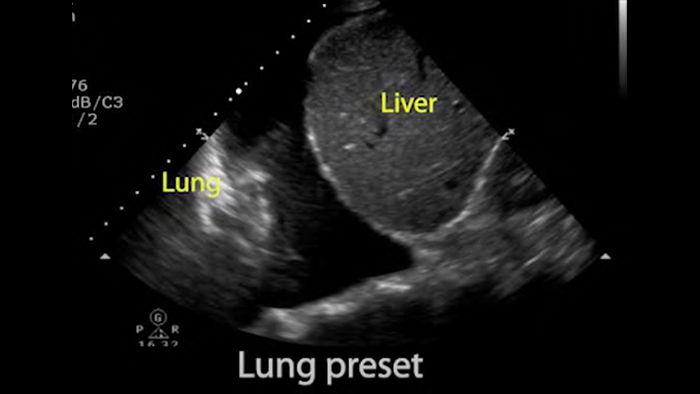

• 4 to 1 MHz extended operating frequency range • 2D, color Doppler, M-mode, advanced XRES and multivariate harmonic imaging • High-resolution imaging for abdominal and cardiac applications: Cardiac, OB/GYN, Lung, Abdomen and FAST imaging preset optimizations

From revealing the subtle details of an image to uncovering enriched tissue definition from multiple angles, Lumify can help you make real-time decisions with more confidence from assessment through recovery.